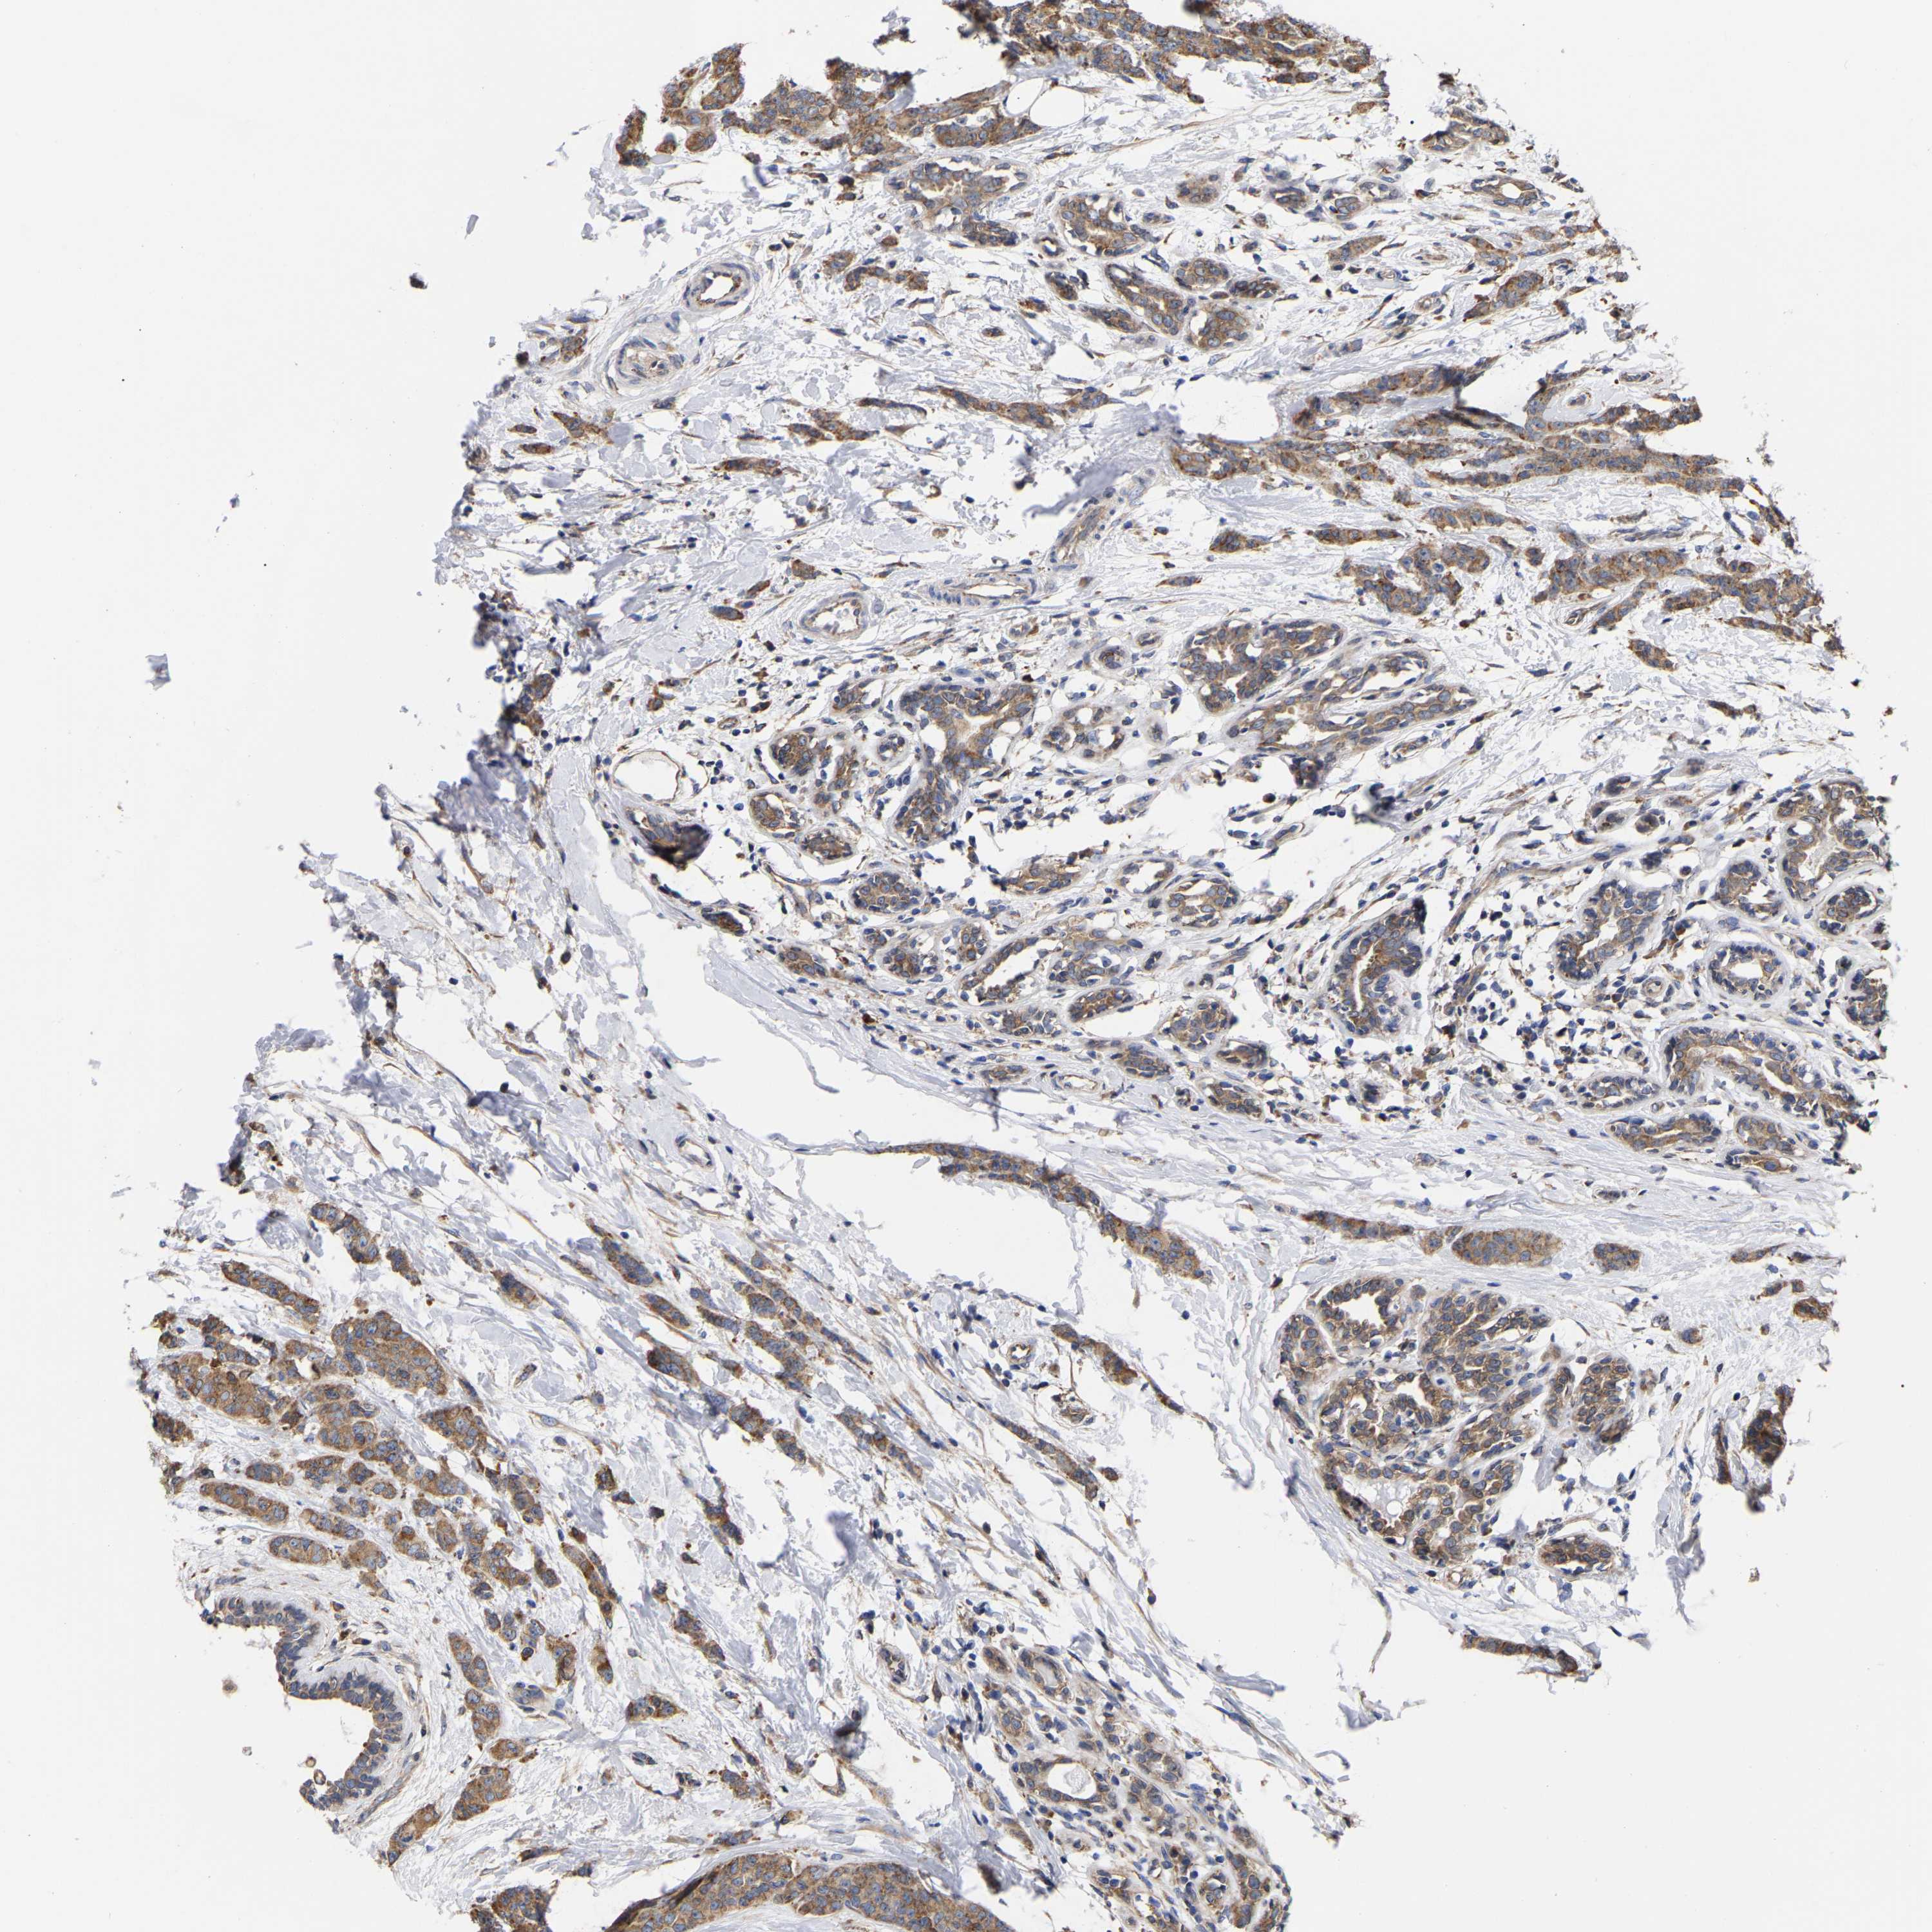

BRCA TCGA BRCA VALIDATION PROTEIN EXPRESSION

ANTIBODIES

AND

VALIDATION